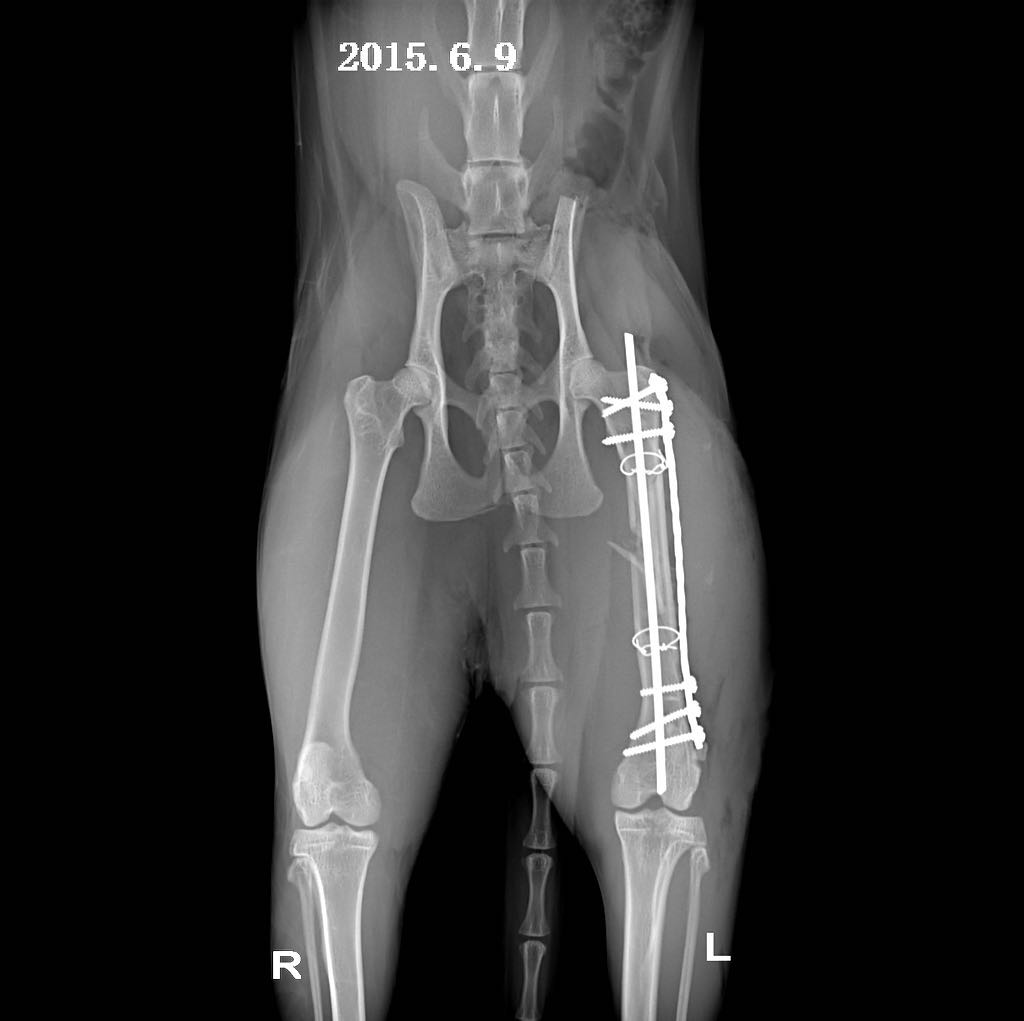

摘 要:动物发生脊椎骨折一般是由大的外力所致:如咬伤、车祸伤或高楼坠伤